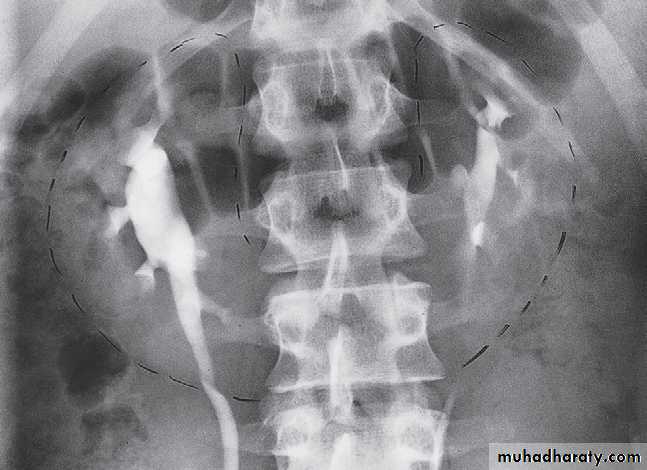

During fetal development the kidneys ascend within the abdomen. An ectopic kidney results if this ascent is halted. They are usually in the lower abdomen and rotated so that the pelvis of the kidney points forward. The ureter is short and travels directly to the bladder. In some cases, both kidneys lie on the same side of the pelvis and are fused.Horseshoe kidney

The kidneys may fail to separate, giving rise to a horseshoe kidney. Almost invariably it is the lower poles that remain fused .Inherited cystic disease of the kidneys